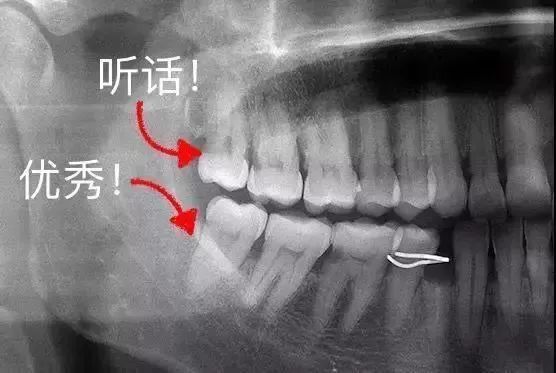

③ 叛逆少年型

什么叫做“叛逆少年型”?看看下面的图片感受下——

图片智齿被阻生的不同状态